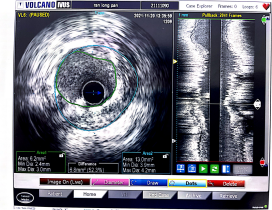

第2例是一位高龄男性患者,84岁冉爷爷1月前因“突发胸痛”就诊,诊断为急性心肌梗死,术中造影提示罪犯血管为前降支,右冠近端完全闭塞,考虑慢性闭塞性病变,行急诊PCI后治疗患者好转出院,医生建议患者择期在IVUS指导下行右冠支架植入术。同样,在陈元友主任的指导下,王欣医师行双侧造影,在钢丝通过闭塞病变后,将IVUS导管放置在血管远端,采取自动回撤模式,可见闭塞处主要为纤维病变,测得管腔最狭窄面积为2.5mm2,病变长度达34.7mm,已经达到介入手术指征,在右冠长病变处成功植入1枚支架,术后IVUS测得最狭窄处管腔面积为6.2mm2,,IVUS及冠脉造影提示术后支架贴壁良好,远端血流恢复正常,患者术后恢复良好。见图2、图3。

图2(左图为术前,右图为术后)